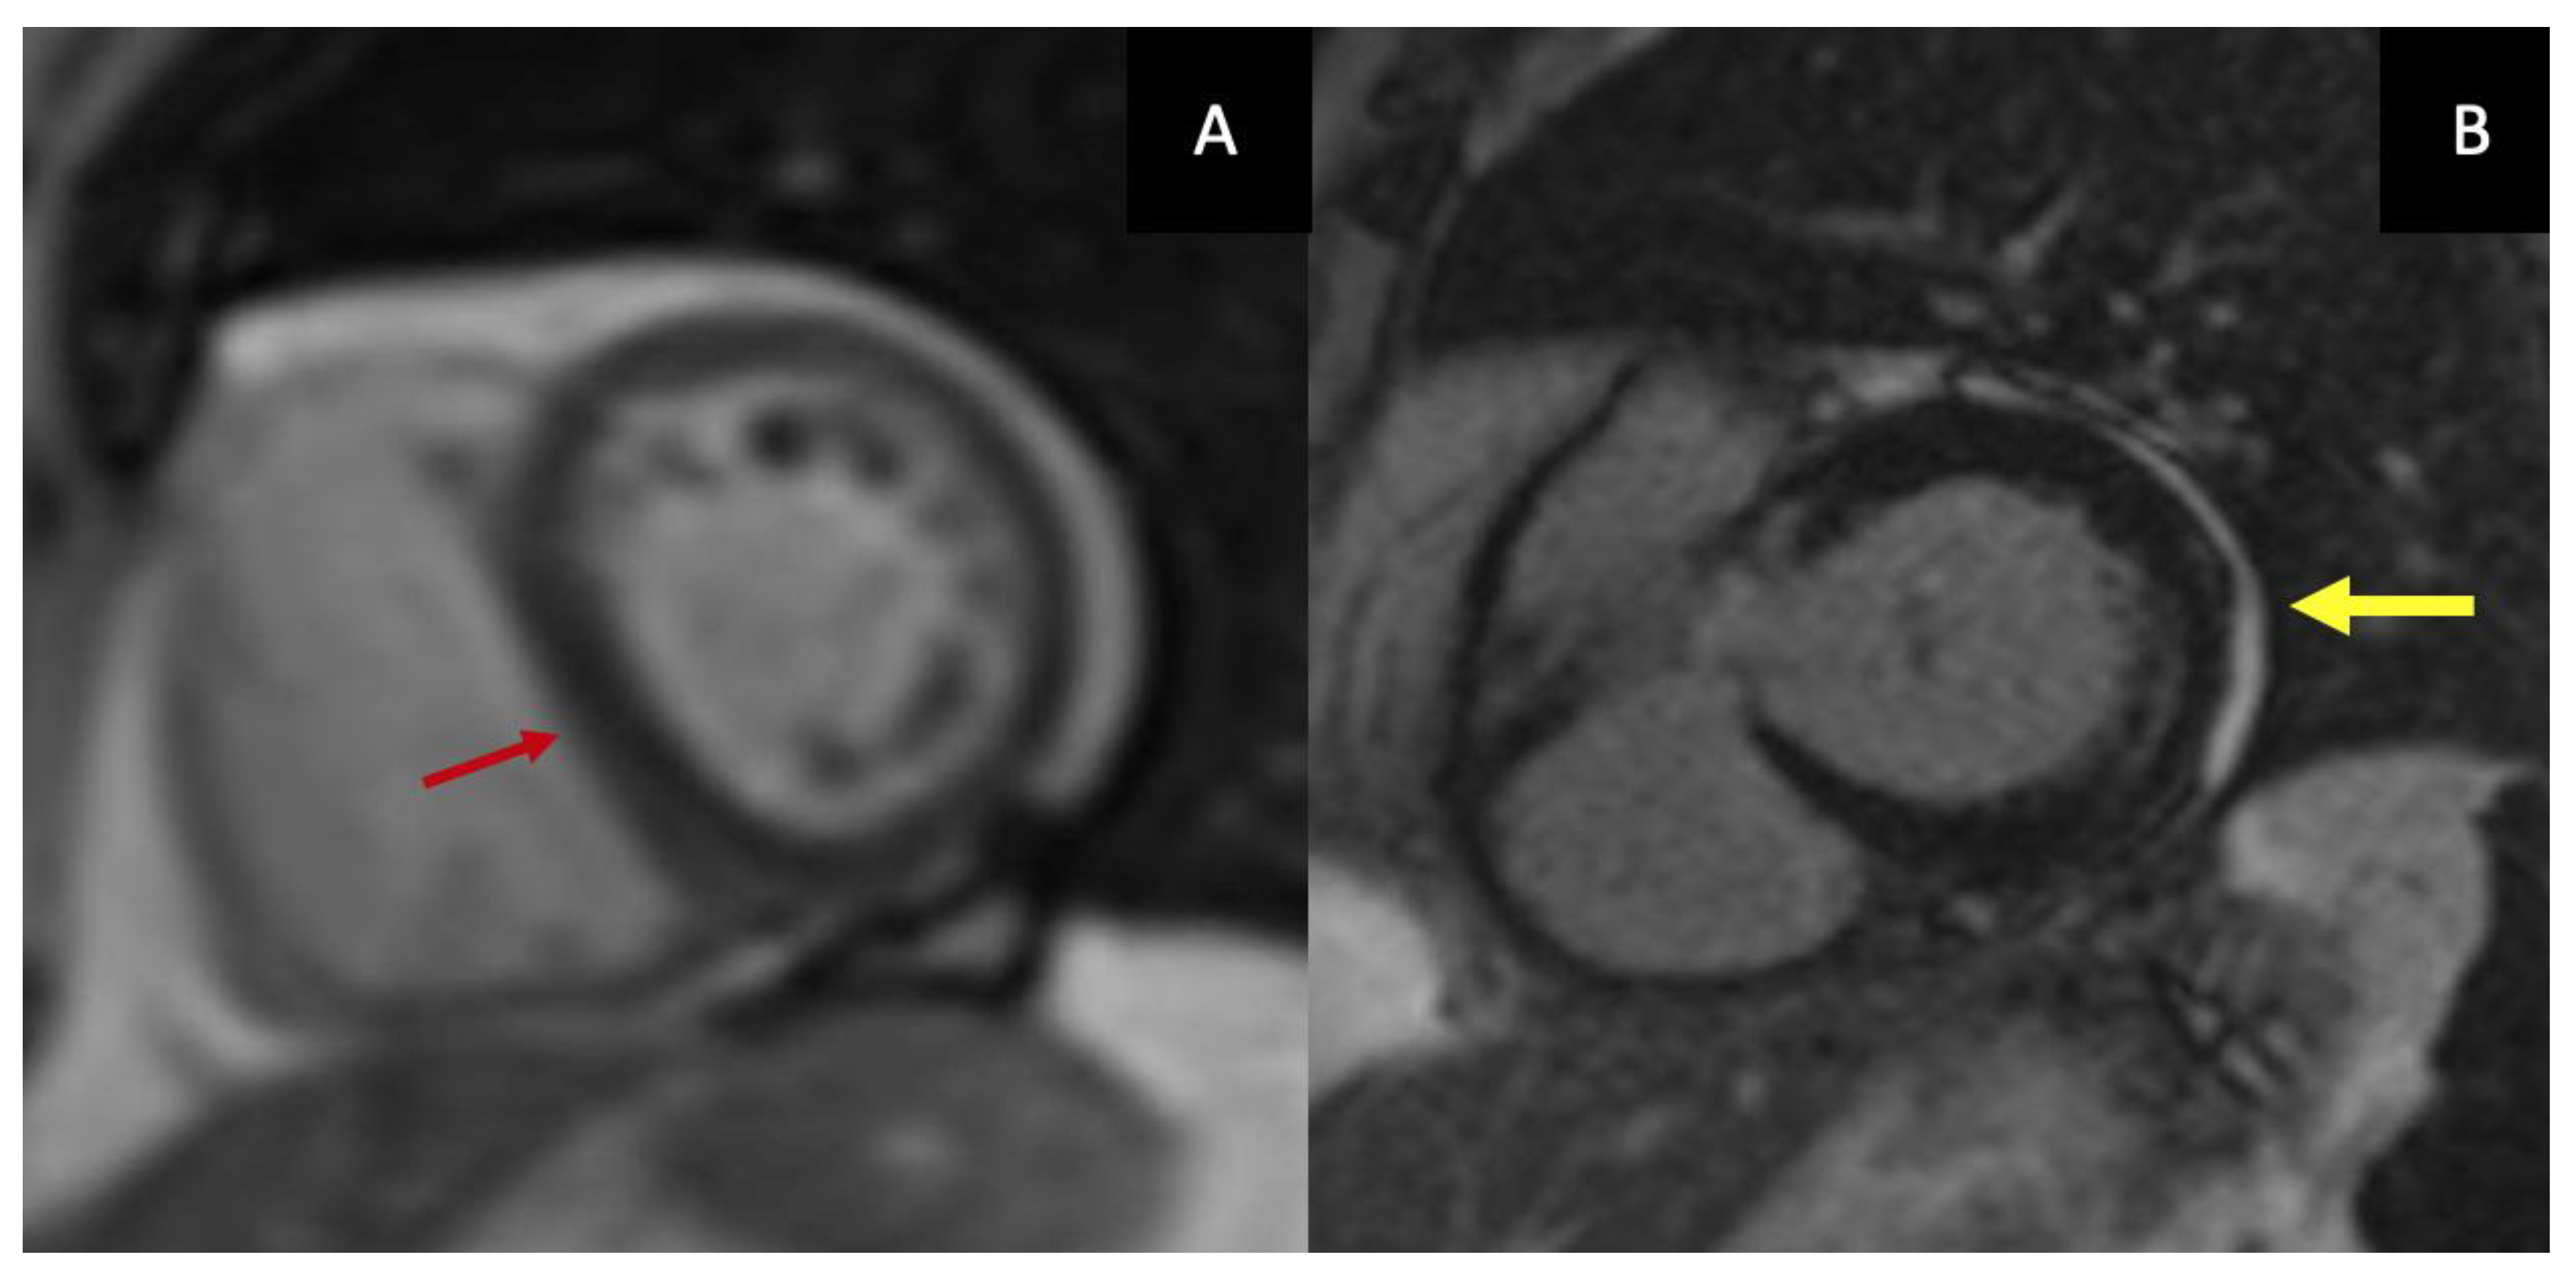

Left ventricular (LV) systolic function, as assessed by LV ejection fraction, is typically preserved in CP. One of the hallmark echocardiographic features is respirophasic interventricular septal motion, which can be observed on both M-mode and 2D echocardiography (Figure 1.A,B). This phenomenon is induced by abrupt changes in ventricular volumes and reflects enhanced ventricular interdependence. During early inspiration, reduced LV filling leads to a sudden leftward shift of the interventricular septum, whereas during expiration, improved LV filling allows the septum to return toward its normal position. This hemodynamic abnormality results in inspiratory septal shift to the left, a plethoric inferior vena cava, and late-diastolic expiratory flow reversal in the hepatic veins (9–10).

Doppler echocardiography provides further insights into diastolic filling dynamics. Because LV diastolic pressure is elevated and virtually all LV filling occurs in early diastole, transmitral inflow typically demonstrates an increased E-wave velocity with a shortened deceleration time, usually less than 160 ms, and a small or absent A-wave. With inspiration, dissociation between intrathoracic and intracardiac pressures results in a decrease in the initial driving pressure for LV filling. Consequently, peak mitral E-wave velocity decreases by more than 25% during the first beat of inspiration, accompanied by prolongation of the isovolumic relaxation time, usually exceeding 20% (Figure 1.C). Ventricular interdependence produces reciprocal changes in right-sided filling, with an inspiratory increase in peak tricuspid E-wave velocity greater than 40%. Reverse changes occur during expiration in both ventricles [11].

Figure 1. Ecocardiography findings in CP: respirophasic interventricular septal motion observed on both 2D echocardiography (A) and M-mode (B); respiratory variation in transmitral inflow (C); Measurement of pericardial thickness by two-dimensional echocardiography (D).